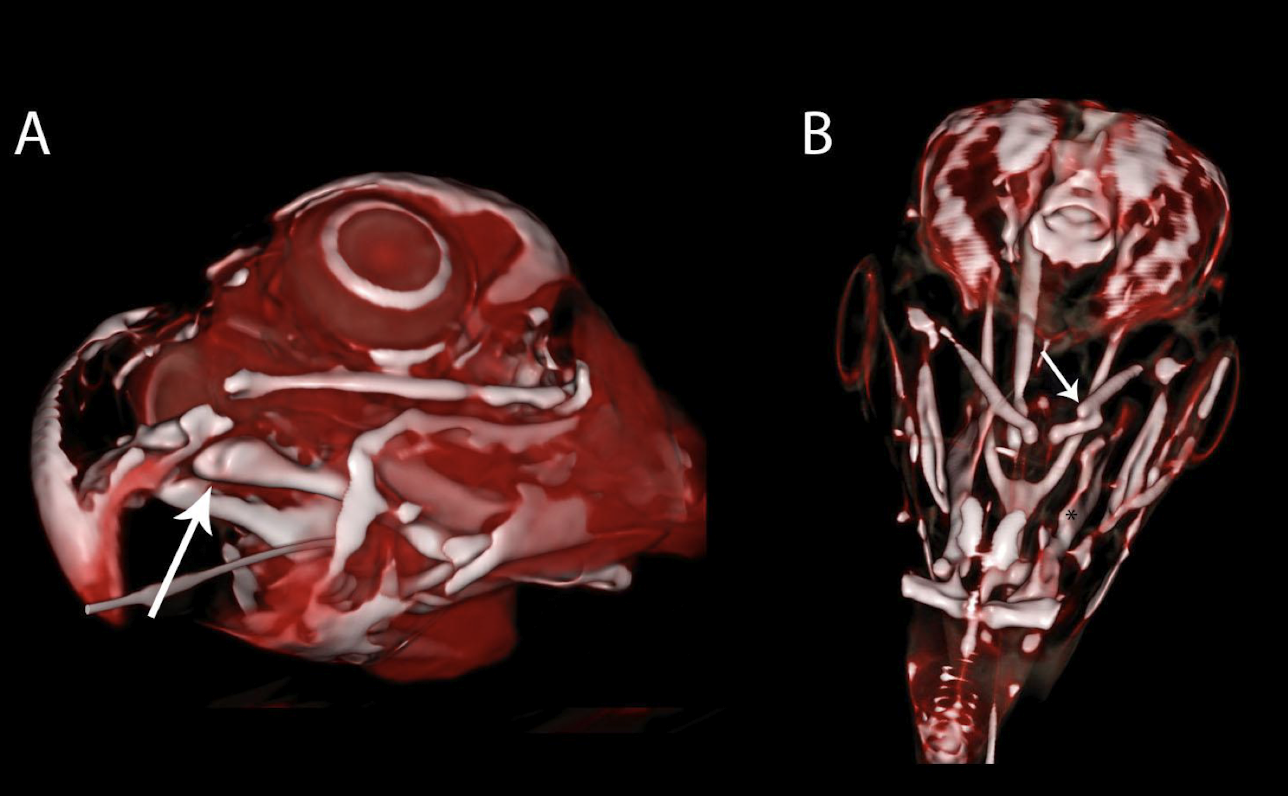

What advanced imaging modality is better for visualizing the avian skull than radiography?

Computed Tomography (CT)

What are the primary indications for using CT in avian diagnostics?

When radiographs are insufficient, for skull fractures, upper respiratory disease, and arterial calcification.